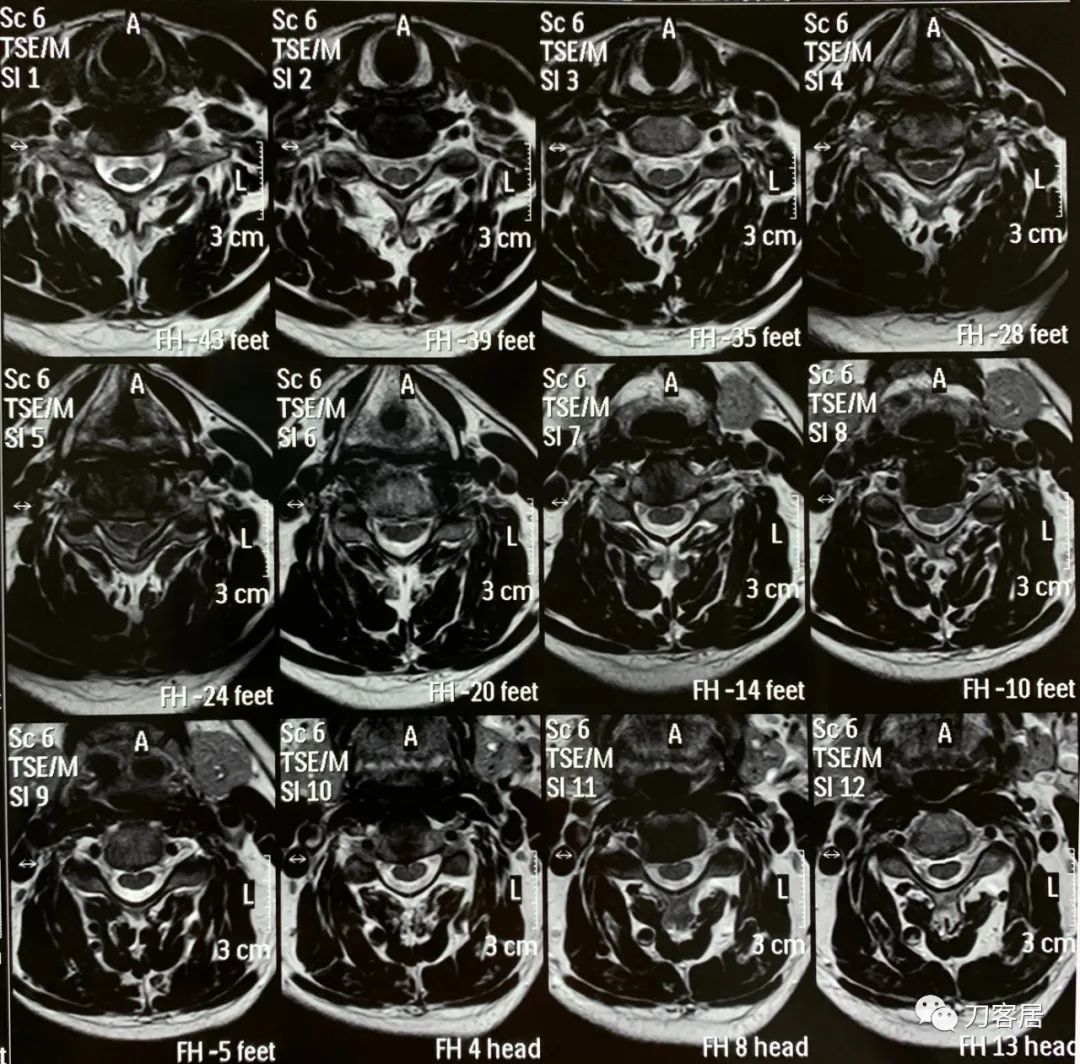

自带颈椎MRI颈5-6退变性滑脱,颈5椎体后移,不稳,但患者无明确的神经损伤表现,且保守治疗有效,暂不考虑手术治疗。腰椎MRI及CT未见严重之椎间盘突出及椎管狭窄,腰椎失稳。

图12. 20190409-QHM-C-A医院-颈椎MRI01

图13. 20190409-QHM-C-A医院-颈椎MRI02

图14. 20190409-QHM-C-A医院-颈椎MRI03

图15. 20190409-QHM-C-A医院-颈椎MRI04